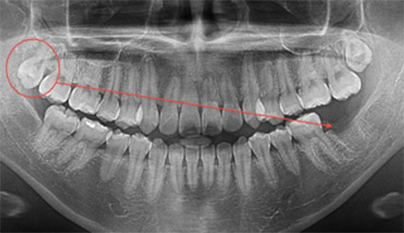

CASE

左下奥歯の虫歯が大きく被せ物が取れてきた右上の親知らずを 移植希望の30歳男性

BEFORE

金属の被せ物が取れて、歯の根の方まで虫歯が進行してしまっているため抜歯をしました。

初診時のレントゲン写真です。 向かって右から2番目。歯が割れているため、根のまわりが黒くなっています。 ここにカラー写真の向かって右から1番目の親知らずを移植します。